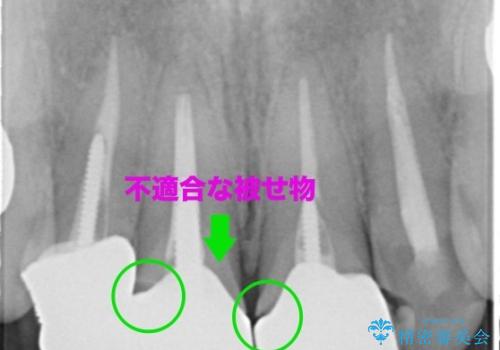

また、隣の歯も被せ物の適合が悪く予後がよくないので根管治療(保険)を行い、セラミックの被せ物で治療を行いました。

適合が良い被せ物が入りました。

被せ物と歯質に隙間があると細菌が入り込むために虫歯になるリスクが高くなります。